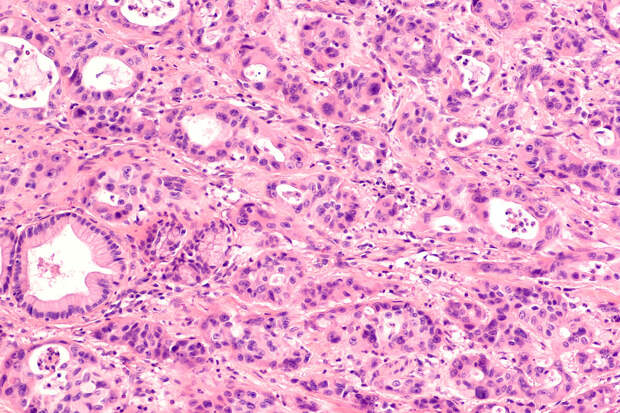

И уже давно описаны генетические мутации для большей части типов рака, однако иногда ученые не могут связать рак с какой-то из генетических мутаций. В этом случае мы говорим об эпигенетических факторах развития рака. То есть у нас нет в генах мутаций, но при этом они все равно неправильно работают и приводят к развитию рака", – рассказал "Газете.Ru" старший научный сотрудник ИБГ РАН Максим Ерохин.В рамках работы ученые сосредоточилась на изучении эпигенетических факторов группы белков-репрессоров Polycomb, которые могут изменять активность генов. Если работу этой генетической конструкции нарушить под воздействием внешних факторов, то в клетках происходят изменения, – они встают на раковый путь развития.

"В нашей работе мы провели эксперимент с мухами дрозофилами. Мы оставили на один день мух в повышенной температуре (29°C), затем мы возвратили их в нормальные условия обитания – при нормальной, комнатной температуре 25°C. Но это кратковременное повышение температуры привело к нарушению работы репрессоров (особых белков), в результате чего у мух развился рак. Возвращение в нормальные условия не остановило патологический процесс. Если мы один раз активировали этот эпигенетический фактор, то клетки становились на раковый путь развития.

При этом никаких генетических мутаций у них не было", – объяснил Ерохин.По словам специалиста, эти белки-репрессоры есть у всех многоклеточных организмов, включая человека. Поэтому потенциально курение или чрезмерное употребление алкоголя могут привести к развитию рака.